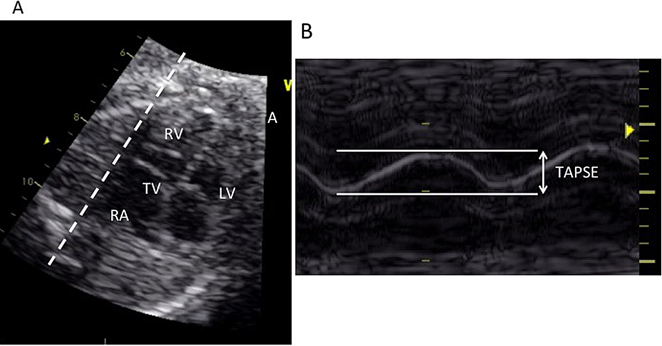

いわゆるレントゲンの心胸郭比に相当する,グローバルな心機能の指標である.計測には総心横径(total cardiac dimension: TCD)と心胸郭面積比(cardiothoracic area ratio: CTAR)がある.TCDは四腔断面において,三尖弁付着部の心外膜から僧房弁付着部の心外膜までを測定したもので,22週以降では数週mmが正常値とされている.CTARは四腔断面で心膜外側をトレースした心臓の面積を脊柱や肋骨を含み,皮膚や筋肉を含まない胸郭の面積で除して求められる (Fig. 1).簡便のため両方を楕円で近似したellipse法が多く用いられる.正常は0.20~0.35.

Fig. 1 Measurement of the cardiothoracic area ratio

A four-chamber view of the fetal heart. The thoracic area is indicated by a solid line, and the cardiac area was by a dotted line. (A: anterior, L: left, R: right, P: posterior)